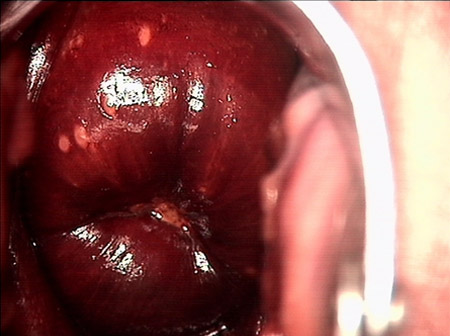

• CIN 2-3CIN 2-3

• CIN 2-3 碘著色后CIN 2-3 碘著色后